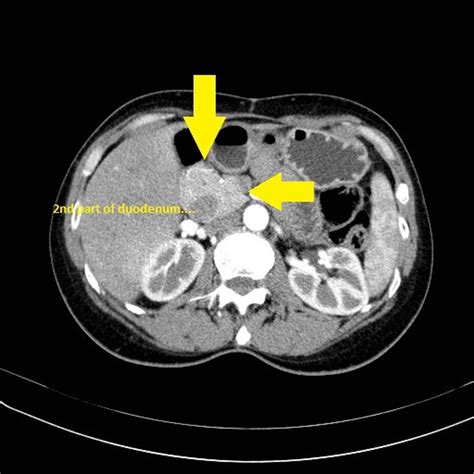

Interpreting CT Scan Results

After the Pancreatic Adenocarcinoma CT Scan, a radiologist will review the images to look for any signs of pancreatic adenocarcinoma. The results will be sent to the referring physician, who will discuss them with the patient. The scan results can provide valuable information, including:

• The presence and location of any tumors.

• The size and shape of the tumor.

• Whether the tumor has spread to nearby organs or lymph nodes.

• Any other abnormalities in the pancreas or surrounding tissues.

If a tumor is detected, further tests such as a biopsy may be recommended to confirm the diagnosis and determine the type of cancer. The biopsy involves taking a small sample of tissue from the tumor for laboratory analysis.